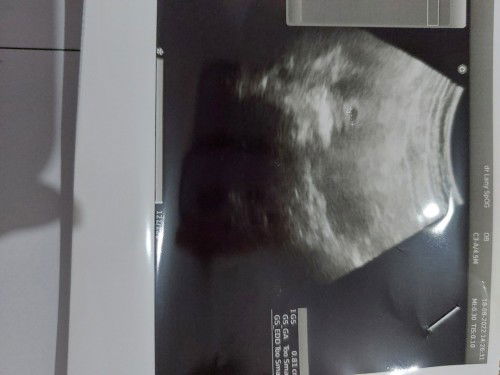

Bund mau nanya hpht 18 feb skrg udh 9w Terakhir usg 6w udh keliatan ada janin nya. Trs blm usg lg, yg jd prtanyaan knpa dr awal telat di tespek sampai skrg hasilnya samar satu, gak garis tebal semua? Apa itu tidak apa2 bun ada yg prnh gini jg? Soalnya sempet kepikiran jg krn pernh keguguran hmil yg kmrn#seriusnanya #bantusharing #ingintahu 🥺